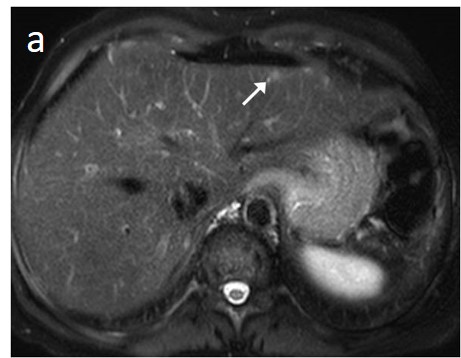

As mentioned before, the radiological hallmark that enables a confident non-histological diagnosis of HCC is the combination of hypervascularity on the arterial phase and hypoperfusion on the portal phase; as with CT, this “wash-in/wash-out” pattern is indispensable on MRI as well. According to the LI-RADS criteria, no lesion without hyperenhancement on the arterial phase can be definitely characterized as HCC; hyperenhancement has to be “non-rim”, i.e., not predominantly peripheral (in order to differentiate from metastases or cholangiocarcinoma) [51]. However, up to 40% of HCCs show no hypervascularity on the arterial phase, and these mainly represent early or poorly-differentiated HCCs [131,132]. Moreover, 40–60% of small HCCs lack wash-out during the portal phase [133,134] (Figure 10). Additional major and ancillary features are employed to help characterize the lesion and assign a LI-RADS category to it.

Figure 10. Evolution of a cirrhotic nodule into HCC. No suspicious lesions are identified on the T2 (a) and DWI (b) sequence of this 66-year-old man with cirrhosis due to hepatitis B infection. On the follow-up scan, performed 3 months later, increased T2 signal (c) is now observed in a nodule in segment V, which is associated with diffusion restriction (arrow) (d). After contrast administration, arterial enhancements (e) without delayed wash-out (f) are seen; absence of wash-out is frequent in early HCCs.